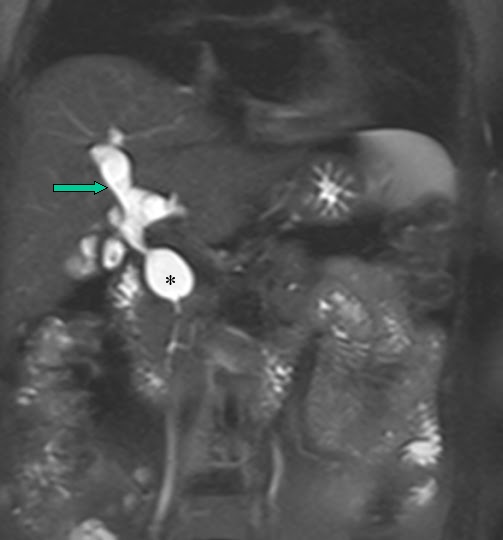

From www.researchgate.net

MRCP showing a type Ic choledochal cyst with a dilated pancreatic duct Type Ic Choledochal Cyst Biliary cysts, also termed choledochal malformations, are cystic dilations that may occur singly or in multiples throughout. Characterized by fusiform dilation of the extrahepatic bile duct. Choledochal cyst is a congenital cystic dilation of a part of bile duct that occurs most commonly in the main part of common. Type i cysts are a dilatation of the extrahepatic bile duct.. Type Ic Choledochal Cyst.